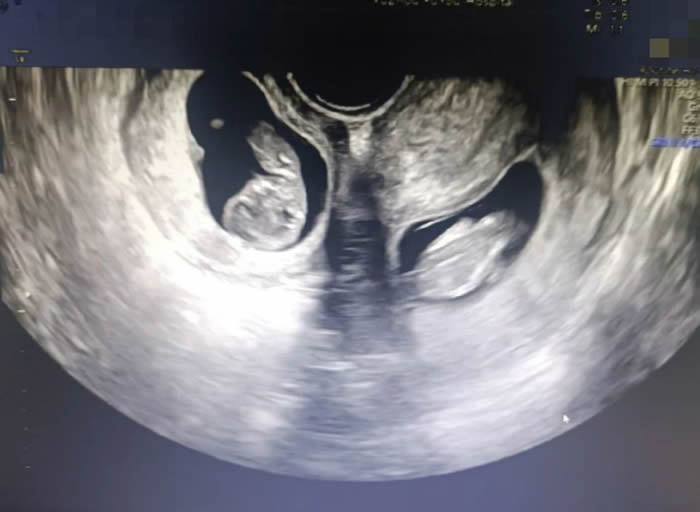

更令人意外的是,早孕期超聲提示,曉曉腹中竟有兩個胎兒,且兩個孩子各居“一室”,互不干擾。“在我近30的職業(yè)生涯中,還從未遇到過雙子宮雙胞胎的孕婦。雙子宮女性妊娠風(fēng)險非常多,很可能會出現(xiàn)早產(chǎn)、胎兒生長受限、子宮破裂等情況,每種風(fēng)險都不容小覷。”產(chǎn)科九病區(qū)主任吳惠瑩如是說。

7點(diǎn)50分,一場生命與時間的賽跑拉開序幕。與普通的雙胎剖宮產(chǎn)手術(shù)不同,此次手術(shù)需要分別在曉曉的兩個子宮上切口取出胎兒。

早早等在一旁的新生兒科醫(yī)生立刻為兩個孩子進(jìn)行檢查,隨后轉(zhuǎn)入新生兒病房進(jìn)行救治。為了預(yù)防產(chǎn)后出血,取出龍鳳胎后,沙小龍醫(yī)生第一時間用藥促進(jìn)子宮及時收縮,兩個子宮緊緊貼在一起,形成了一個完整的心型。